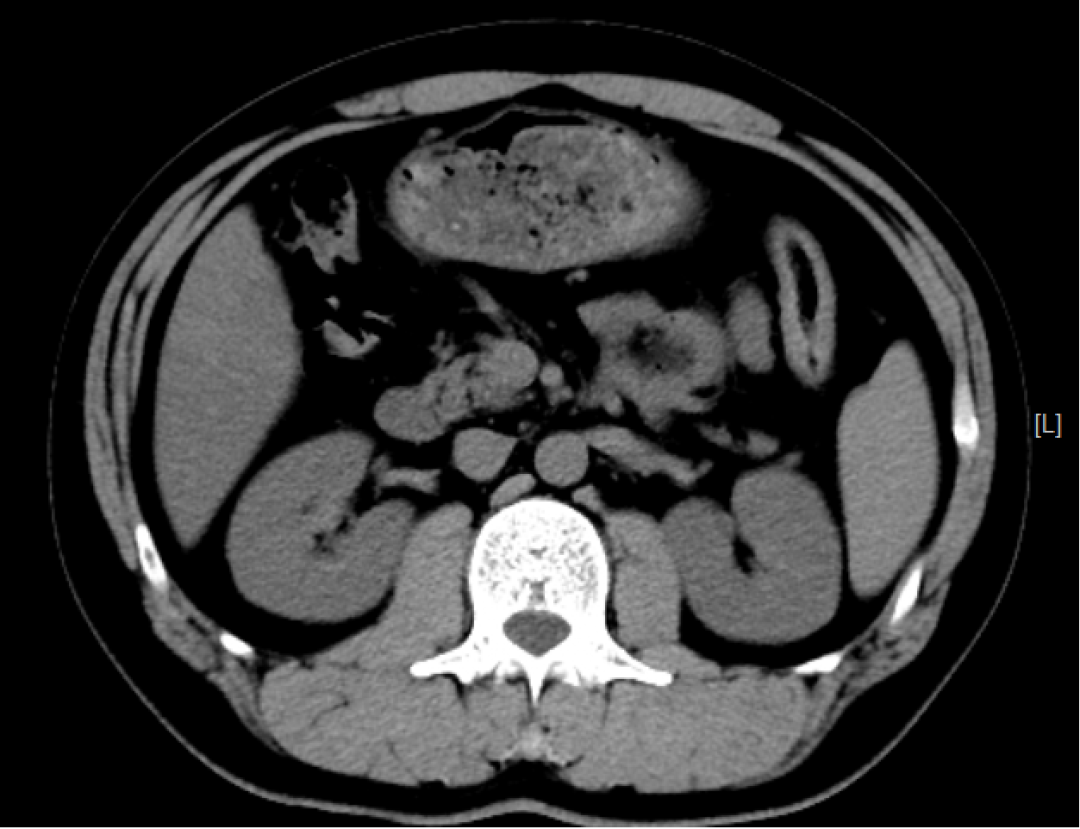

检查应用范围:从头到脚,均可进行CT平扫,主要运用于头颅、颈部、胸部、腹部、脊柱、盆腔、四肢等部位。特别是高分辨率胸部CT,在检查肺部小结节时,运用非常广泛,CT检查脑出血也有相当的优势,另外微小的骨折、大部分器官的病变都能够看到。

优点:相较DR,CT的密度分辨率更高,可以显示DR检查不能发现或容易遗漏的病变。

注意:部分疾病不能做CT增强检查,如:肝、肾功能不全、甲状腺功能异常、碘对比对剂过敏、重度荨麻疹等,需要CT增强检查的患者需要临床医生评判后才可进行。